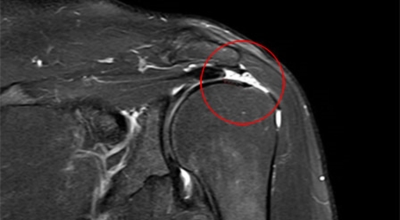

회전근개 증후군은 회전근개에 변형과 파열이 생긴 질환을 말합니다. 회전근개란 어깨와 팔을 연결하는 4개의 근육(극상근, 극하근, 소원근, 겹갑하근) 또는 힘줄로 이루어져 있는 것으로 보입니다. 어깨 근육통을 막연히 오십견으로 알고 방치하다가 치료 시기가 늦어지는 경우가 있답니다. 적절한 시기에 병원에 가는 것이 필요합니다.

회전근개가 파열되는 경우 어깨에 통증이 생겨나게 되어요. 회전근개는 어깨 회전 운동에 영향을 줌으로 인해 팔을 들어올리는 동작에 제약이 생기기도 합니다. 이러한 증상은 오십견 증상과 비슷하기도 한데요. 수동적 움직임도 제한되는 오십견과는 달리 다른 사람의 도움을 받게 되면 팔을 들어올릴 수 있다는 차이가 있답니다.

상완골두 즉 상완을 구성하는 뼈가 높아져 견봉과 맞닿으면서 뼈끼리 닿아서 관절염이 될 수 있답니다. 최악의 경우 파열이 왔는데 방치하면 탈구로 이어질 수 있기 때문에 조심해야겠습니다. 세팔을 위로 뻗기가 힘듭니다. 본인 스스로가 팔을 못 들어 올리는 상태가 되는데, 다른 사람이 올려주면 올릴 수 있지만 손을 떼어버리면 힘이 빠져서 팔을 떨구게 되어요.